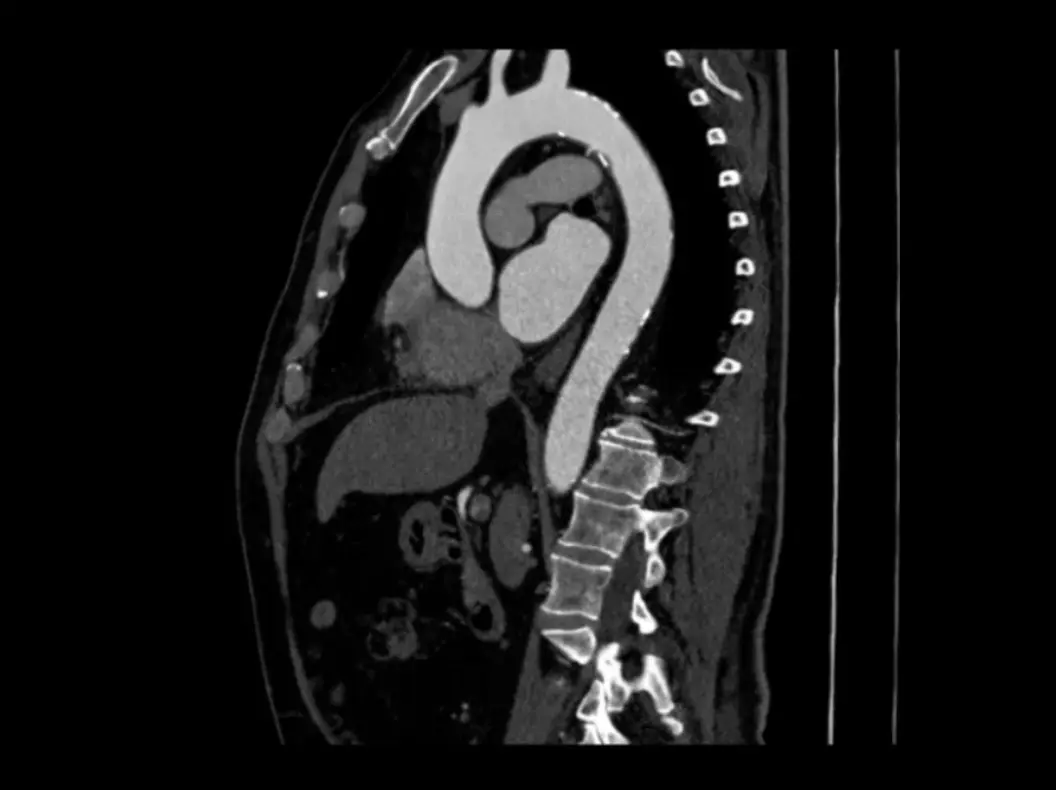

Introducing Rapid Aortic

Your must-have tool for aortic patient management

Rapid Aortic sets the standard for AI in aortic management

AI-driven, accurate and reliable automated measurements, unrivaled longitudinal tracking features, and lab-quality imaging outputs inform clinical decisions and simplify patient surveillance

High-fidelity 3D visualization of CPR, MPR, and volume renderings